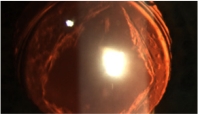

Capsulotomia com Yag Laser:

A aplicação de YAG Laser é indicada para pacientes já operados de catarata e que apresentam redução tardia de visão pela opacificação da membrana remanescente do cristalino original que fica atrás da lente implantada, chamada cápsula posterior. O procedimento é realizado com anestesia tópica (colírio) e o resultado é praticamente imediato.